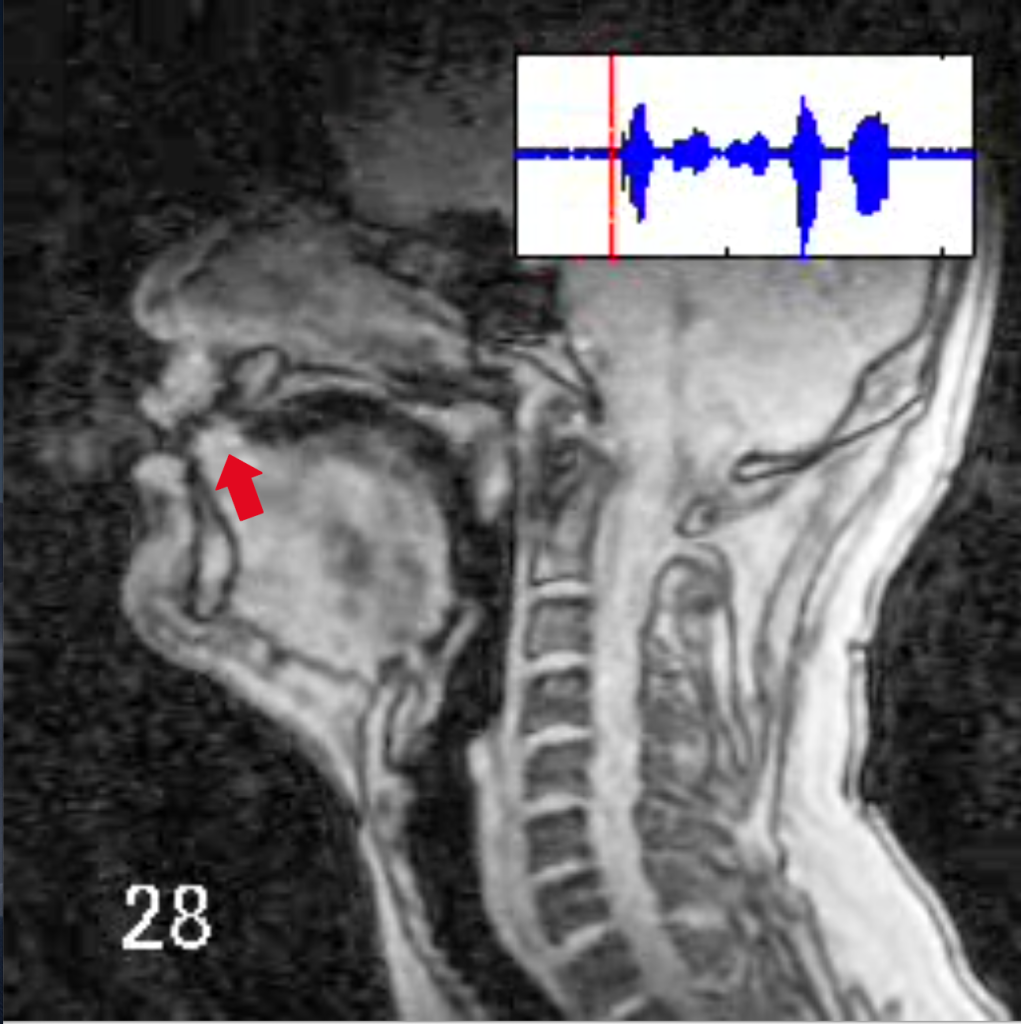

川原 これはMRIっていうんだけれども、知ってる? 病院で使うものだから、あまり馴染みがないかもしれない。だけど音声学者はMRIに入って、人間が発音するときに何が起きているんだろうというのを撮影したりするの。こっちが「か・き・く・け・こ」を発音した時の様子。

MRIの見方の説明をしないとね。この人は左を向いていて、顔の断面図が映っています。真ん中に映っているのが舌。「か・き・く・け・こ」を発音するときに、舌がどう動いているか、ちょっと見てみて。この舌の奥のほうが動いているのがわかる?

川原 「か」は舌の後ろ側が動くんだったね。じゃあ、「がぎぐげご」はどうだろう? MRIを見てみようか。「かきくけこ」とほとんど一緒だね。じゃあ「か」と「が」は何が違うのっていう話になる。